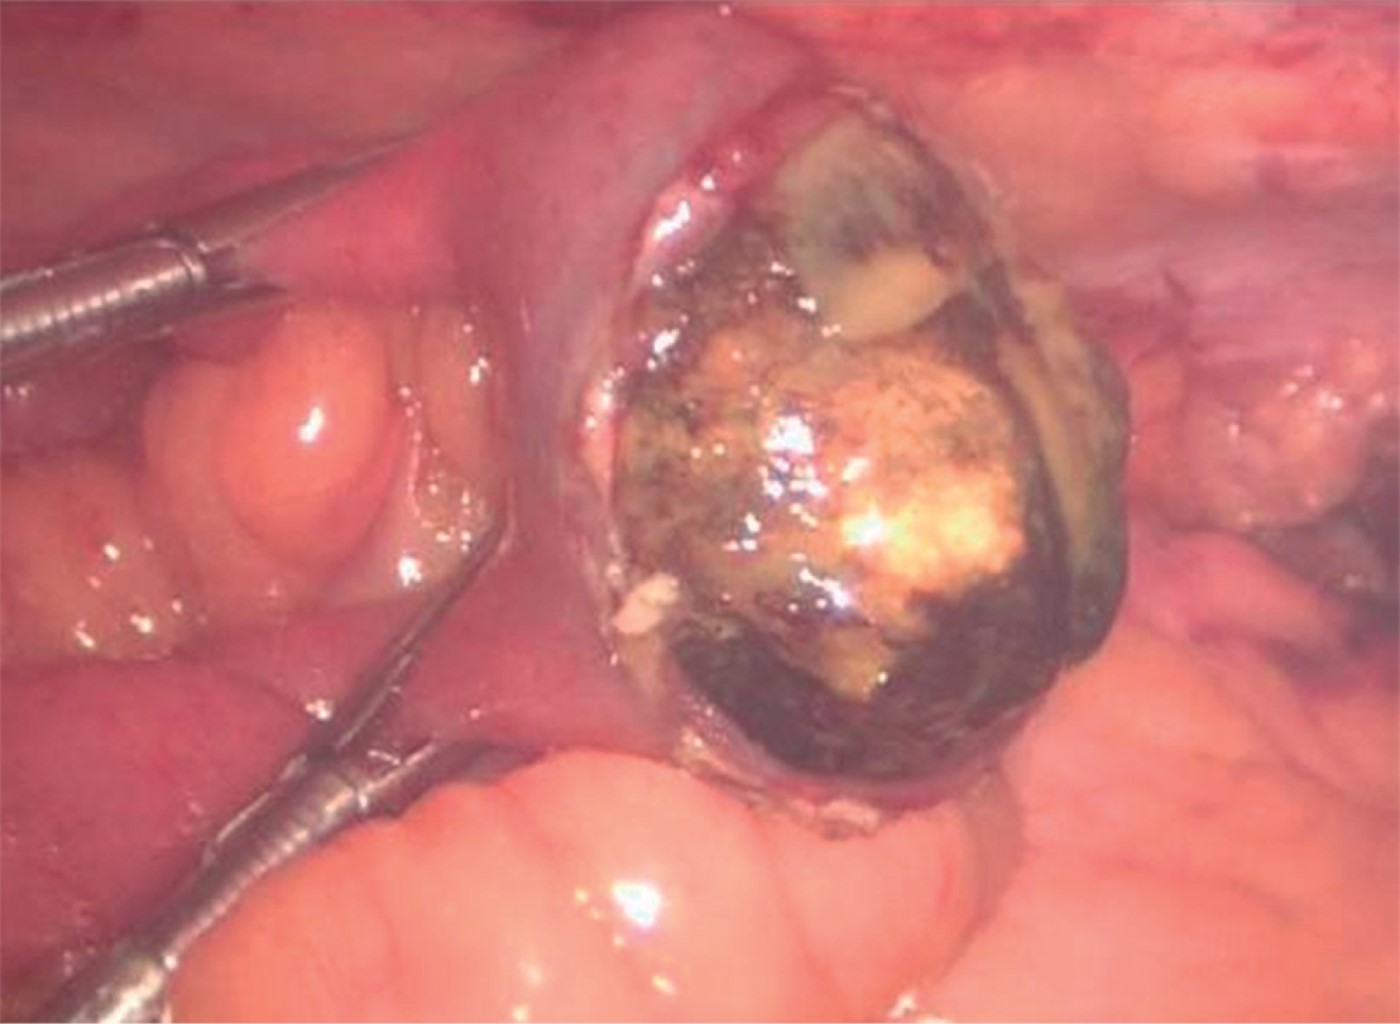

Paciente femenino de 59 años de edad con antecedente de evento vascular cerebral isquémico hace cinco años, diabetes tipo 2 en control con hipoglucemiantes orales (metformina de 850 mg cada 12 horas y glibenclamida de 5 mg cada 24 horas), hernia hiatal sin cirugía y cardiopatía isquémica en control con ácido acetilsalicílico de 100 mg vía oral cada 24 horas y atorvastatina de 40 mg vía oral cada 24 horas. Su padecimiento inicia con náuseas y vómito de contenido gastrointestinal color café, que conduce a intolerancia a la vía oral acompañada de dolor en epigastrio referido en intensidad 7/10, automedicada con antiespasmódicos y antiinflamatorios no esteroideos (AINE), con mejoría parcial; 48 horas posteriores al inicio de los síntomas, incrementa la intensidad del dolor y presenta distensión abdominal, así como incapacidad de canalizar gases por recto. A su ingreso al servicio de urgencias, la paciente se encontró deshidratada, con abdomen distendido, doloroso a la palpación superficial y ruidos metálicos. Se colocó sonda nasogástrica cuyo gasto fue fecaloide. Bioquímicamente con falla renal aguda, desequilibrio hidroelectrolítico y acidosis metabólica. Radiográficamente con asas de intestino delgado dilatadas, neumobilia (Figura 1) y datos de oclusión intestinal. Ante esto, se decide exploración quirúrgica laparoscópica, observándose dilatación de asas de intestino delgado hasta un segmento de íleon, localizado a 150 cm de válvula ileocecal, donde se observa una protuberancia que marca el fin de la dilatación intestinal y que corresponde a un lito de 3.5 cm enclavado; se realiza enterotomía, extracción de lito y cierre primario en un plano, sutura continua con prolene 2-0 (Figura 2). En el transoperatorio, la paciente se comportó con inestabilidad hemodinámica, por lo que fue necesario iniciar apoyo con norepinefrina (16 mg en 250 ml de solución salina al 0.9%) a 8 ml/h, dosis, que fue en descenso hasta su retiro total en 48 horas. Posteriormente, evolucionó de manera favorable, siendo egresada al quinto día manteniendo estabilidad hemodinámica, tolerando la vía oral, sin datos de respuesta inflamatoria sistémica. Actualmente, a un año de la cirugía, continúa en seguimiento por consulta externa como paciente ambulatoria sin haber presentado complicaciones relacionadas al evento quirúrgico.

Figura 2